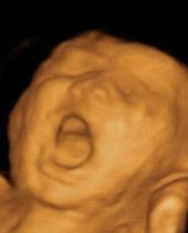

这个宝宝看起来正在大喊,右边这个宝宝则在思考人生。